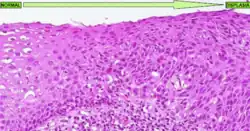

A displasia é essencialmente uma desespecialização do tecido, ele fica mais imaturo e afasta-se do aspeto normal. É frequente que no microscópio seja possível observar em uma displasia:

- Pleomorfismo celular (células com tamanhos e formas diferentes entre si)

- Atipia nuclear (células com núcleo irregular) com hipercromatasia (núcleo mais escuro que indica que o tecido está com alta atividade proliferativa)

- Perda da arquitetura normal do tecido (p. ex.: glandulas irregulares e dismórficas)

- Pseudoestratificação ou estratificação completa de epitélios simples (em monocamada)

- usualmente com perda de polaridade celular, na qual os núcleos podem estar tanto orientados perto do pólo basal como do apical ou ao centro)

- Aumento da relação núcleo/citoplasma (núcleo maior e ou citoplasma mais pequeno)

- Presença de nucléolo quando não é normal naquele tecido tê-lo visível (é um sinal forte de indiferenciação celular também)

- Células binucleadas (é mais raro acontecer, mas deve-se a mitoses muito frequentes aumentando a hipótese de haverem erros na replicação celular)

A displasia pode ter outras caraterísticas específicas para um tecido ou para outro, mas estas são as caraterísticas principais mais comuns à maioria dos tecidos.

Lesão celular reversível desencadeada por fatores irritantes crónicos. Sua alteração pode acontecer na forma, tamanho ou organização de um determinado tecido ou epitélio, podendo variar em três níveis:

- Displasia de alto grau

Quando atinge o nível de alto grau chama-se também carcinoma in situ, que é uma forma precoce de cancro, essencialmente já tem capacidade de invasão mas está ainda em estádio precoce, reduzido à mucosa (no estadiamento TNM, esta lesão é tis).

Os níveis diferem-se com base no quão diferente o tecido está diferente do original, havendo fatores dos supradescritos que são mais preponderantes que outros (como perda de arquitetura tecidular, p. ex.). Há técnicas de imuno-histoquímica (IHQ) que permitem calcular o índice proliferativo com o Ki-67 ou então verificar se genes tumorais estão mutados ou ausentes. Estas técnicas de IHQ, o tipo tumoral, e o estadiamento tumoral, permitem calcular o prognóstico desta lesão.